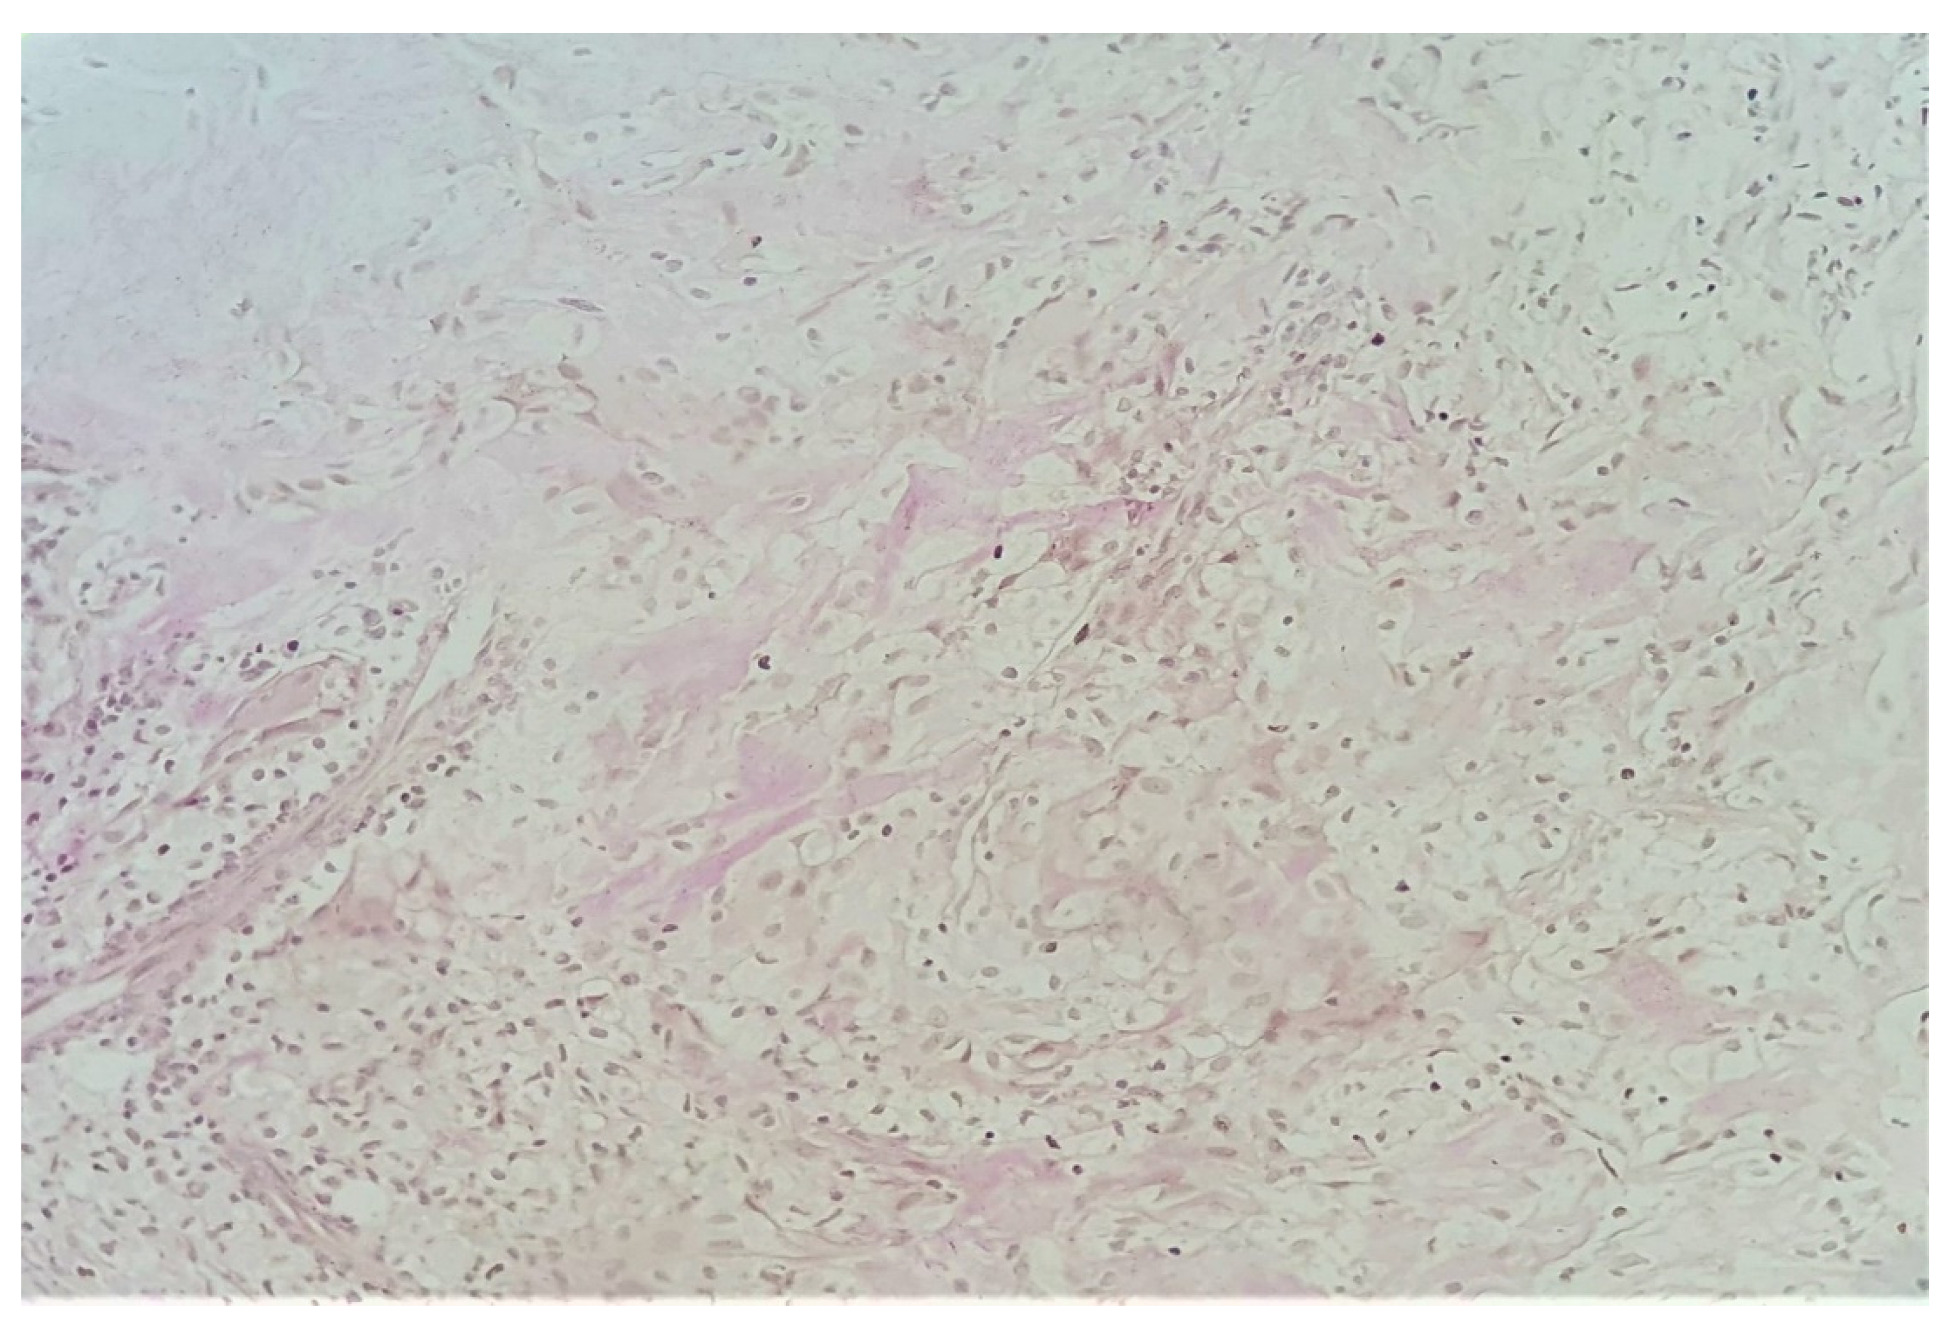

3.2. Histopathological Examination of the Specimen